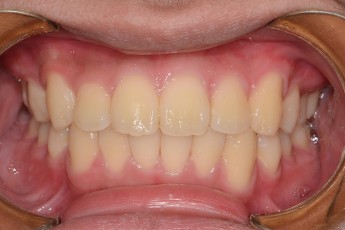

BEFORE & AFTER

- 돌출입교정